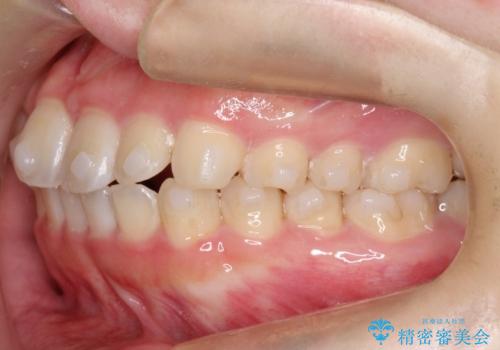

【インビザライン】前歯の凸凹をなおしたい

- 前歯のガタガタを主訴に来院されました。

インビザラインで綺麗な歯並びになり、患者さんには大変満足していただきました。